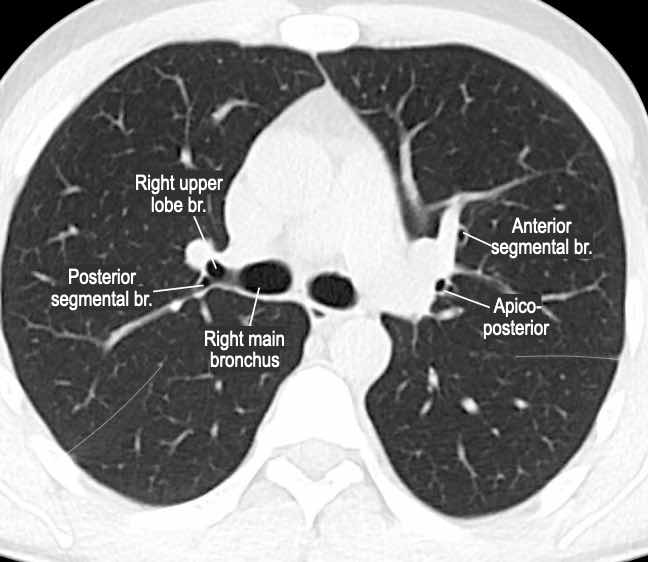

Phế quản trên CT

Cuộn qua các hình ảnh để quan sát khí quản phân chia thành phế quản chính phải và trái, sau đó tiếp tục phân chia thành các phế quản thùy và phế quản phân thùy.